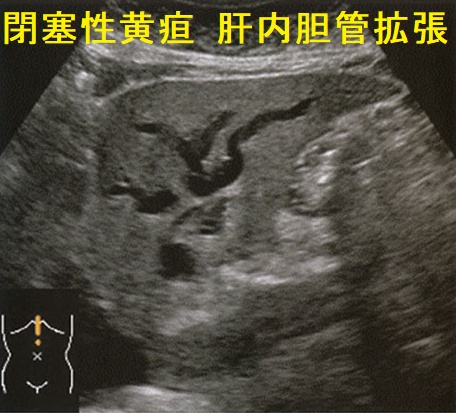

- 総胆管下部は膵臓に抱えられており、閉塞性黄疸に

Courvoisier徴候は、乳頭部癌、胆管癌、膵頭部癌などが原因で胆嚢管分岐部より下部の胆管が閉塞し、腫大した胆嚢を無痛性に触知する徴候です。

- 閉塞性黄疸を伴う